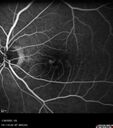

83 year old man Retired aerospace engineer. Blurred vision in both eyes with complex eye history. No acute changes noted by patient. Prior macula-on retinal detachment repair in the right eye a year ago (buckle, vitrectomy, laser, gas, ST Kenalog). Medical Hx: Hypertension, Systemic. Hyperlipidemia. Asthma. Surgical Hx: left shoulder ac separation 2013. Turp 2010. Systemic Meds: Lisinopril, 10 mg oral tablet bid. simvastatin QD. muscinex DM QD. Metformin 100 MG QD. Allergy Medicine. HCTZ QD. PRILOSEC QD. MYBETRIC. MONTULAKAST. Aspirin 81 mg. QUETISPINE 150 MG QD. ESATATOPRAM 20 MG QD. VA OD: Dcc20/50 VA OS: Dcc20/50-2 IOP: TP: OD:15 OS:16 Converted to wet AMD after a single Izervay Treatment

Conversion to Wet AMD after Izervay25 views83 year old man whose left eye had minimal GA and converted from dry to wet AMD after a single Izervay treatment00000